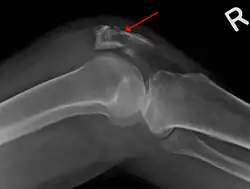

Some people have a normal bipartite patella or two-part patella which can appear as a fracture. The fragment is usually seen in the top outer corner of the patella and can be distinguished from a fracture by being present in both knees.[6]

The patella can break in various ways depending on the way it is injured, and into two or more pieces.[1] Types include transverse, the most common, with one fracture line;[5] marginal; osteochondral; and the rare vertical type, or stellate, where a direct compression force gives rise to a comminuted pattern.[5][7] Patella fractures can be further classified as displaced, where the broken ends of bone do not line up correctly and separate by more than 2mm, or undisplaced and stable where pieces of bone remain in contact with each other.[1][7] If fragments of patella bone stick out from the skin it is known as an open patella fracture, and closed if the overlying skin is intact.[1]